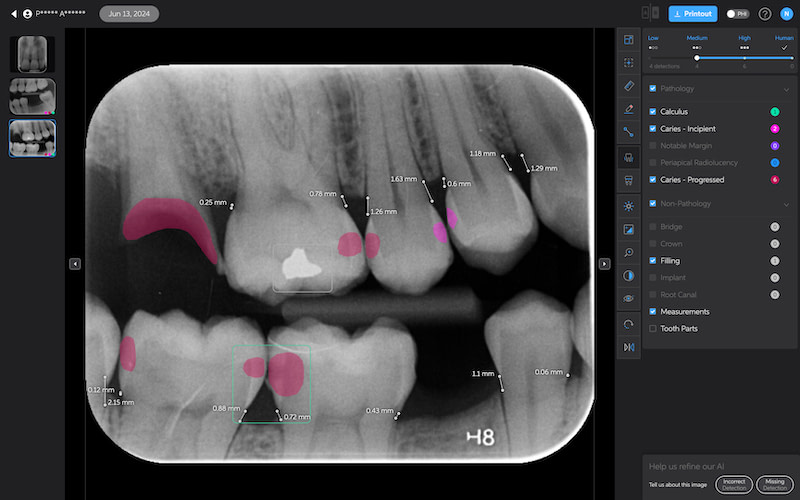

Bone Measurements

The system provides automated measurements from the crest of the bone to the cementoenamel junction (CEJ). These measurements are color-coded to indicate severity:

- White: 0-2.5 mm

- Yellow: 2.5-4 mm

- Amber: >4 mm

This feature is helpful for periodontal assessments, streamlining the process of identifying areas of bone loss. However, it's important to note that image angulation can affect the accuracy of these measurements, a limitation the system acknowledges.

I found these lines to be incredibly useful when describing patients' periodontal health. Cool feature, no doubt.

Calculus Detection

Green squares highlight areas of radiographic calculus. This tool is useful for hygienists and dentists in treatment planning and patient education.

Quite self-explanatory and the system didn't seem to miss often, if ever.

Notable Margins

Purple squares indicate areas of notable margins, such as potential overhangs or open margins on existing restorations.

This is particularly useful as well. I find that patients hate hearing that there is secondary decay at the edge of a crown, for example. And it is always a touchy subject if it is a recent crown done elsewhere. With AI, you are effectively removing yourself and any perceived sales bias from the diagnosis. This is what the AI shows.

Great feature.

Caries Detection

The best for last and arguably the most well-thought-out feature. Especially with the tooth segmentation mode, which makes it easier for patients to understand their diagnosis and treatment plans.

The system uses two shades of pink to indicate potential caries:

- Light pink: Incipient caries (100% in enamel) - we will often review

- Darker magenta: Caries extending into dentin - we need to restore

The system even provides a percentage breakdown of enamel vs. dentin involvement. I have been blown away by its accuracy while using it, and it makes something that feels quite subjective (reading shades of grey) into a science.

This feature is very useful for patient education and deciding between preventive measures and restorative treatment. However, remember that radiographic evidence alone is not always sufficient for a definitive caries diagnosis.